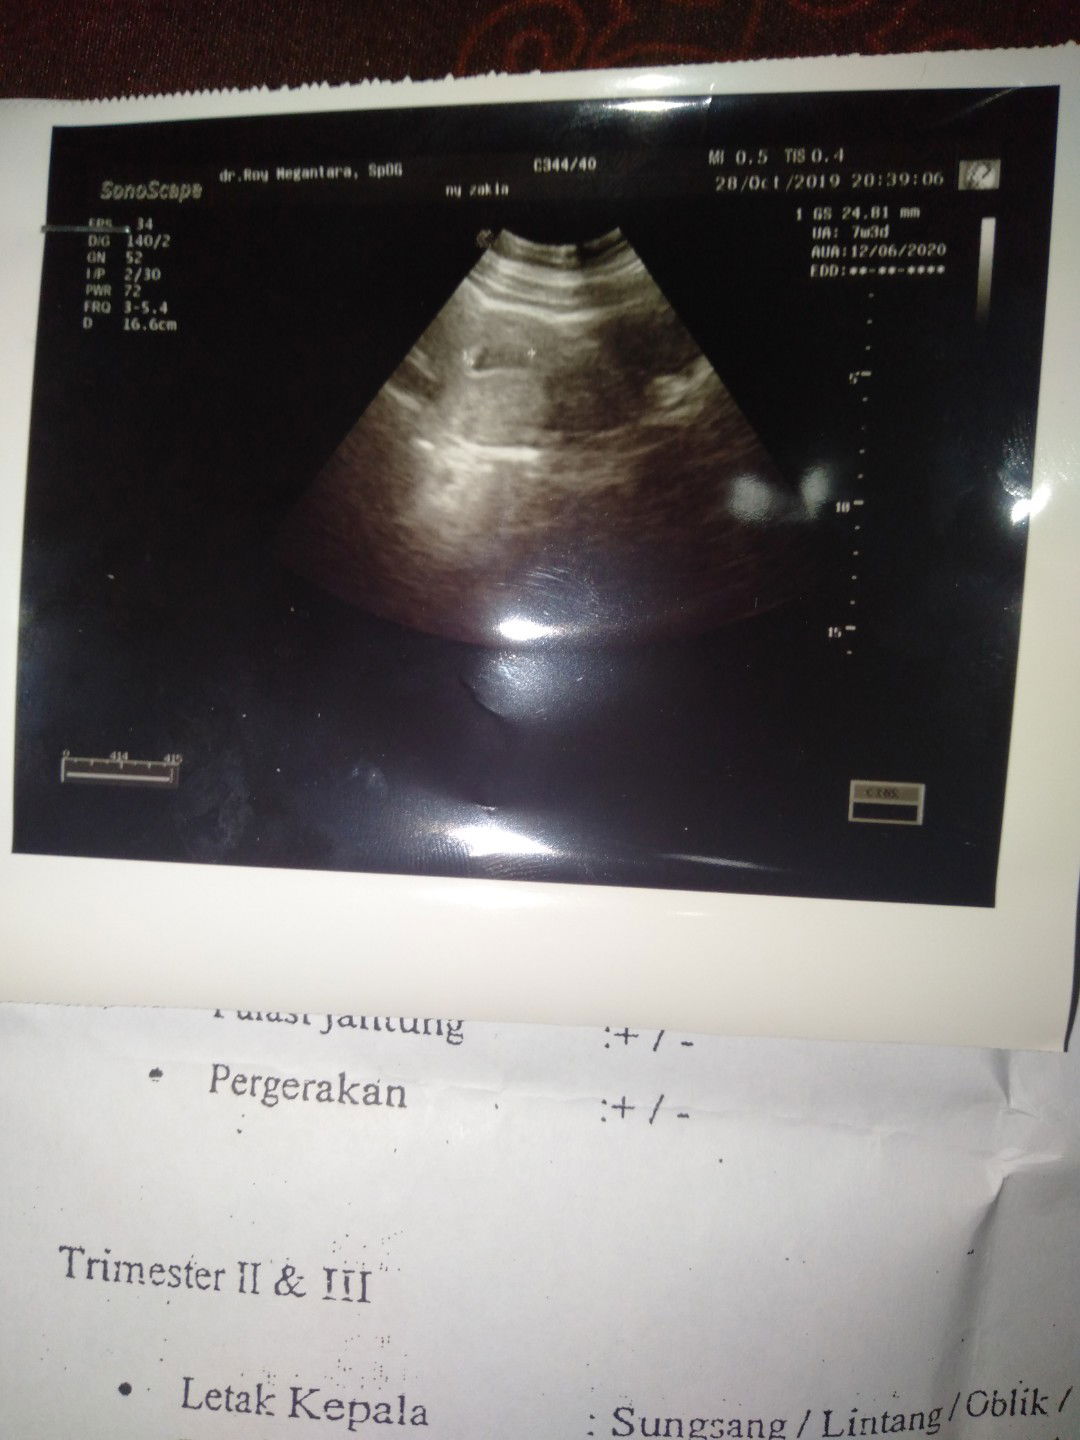

usg 7 week

Pagi Bunda . Saya baru saja semalam USG tp Disni terlihat kantong janin .cuma saya agak bingung membacanya .di layar kan hanya terlihat kantong nya tp di sudut kanan atas ada kotak kecil yg berisi seperti bentuk janin kecil gitu . Apakah itu janinnya atau saya salah ya bacanya? Mohon penjelasannya Bunda bunda.